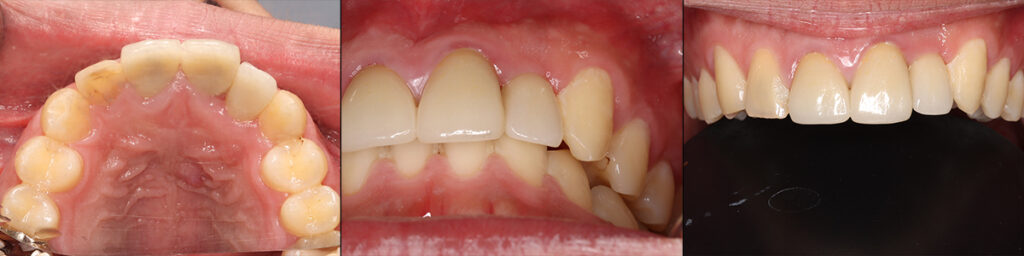

治療直後の上下前歯の被蓋関係と術前の状態

装着後3か月 歯肉が安定化する